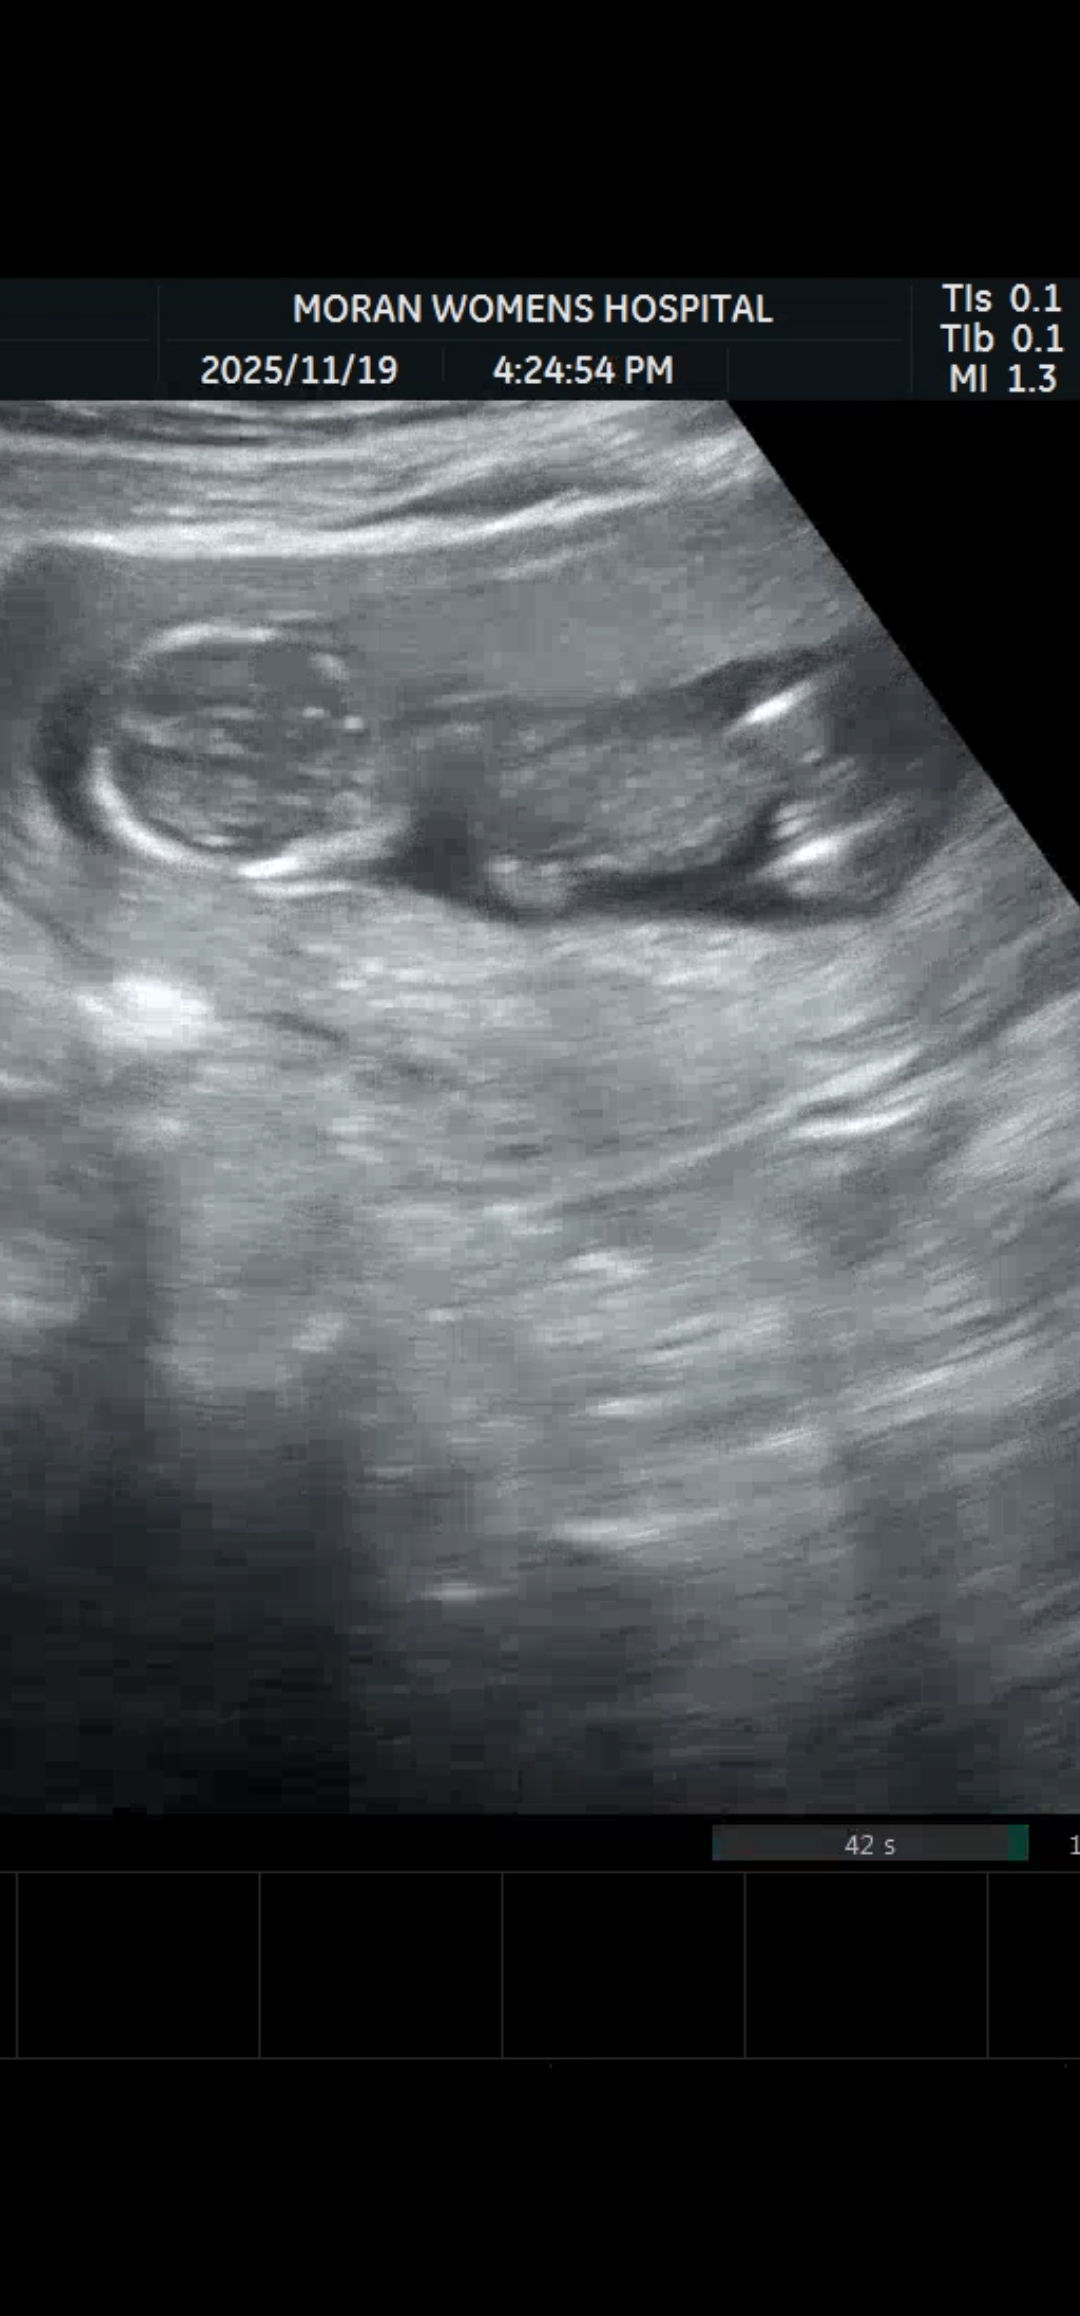

13주 성별이 뭘까요?.?

12주에 각도법 카페에서는 딸에 한표였는데 오늘 병원에서는 아들일거같다고 하네요 🤣